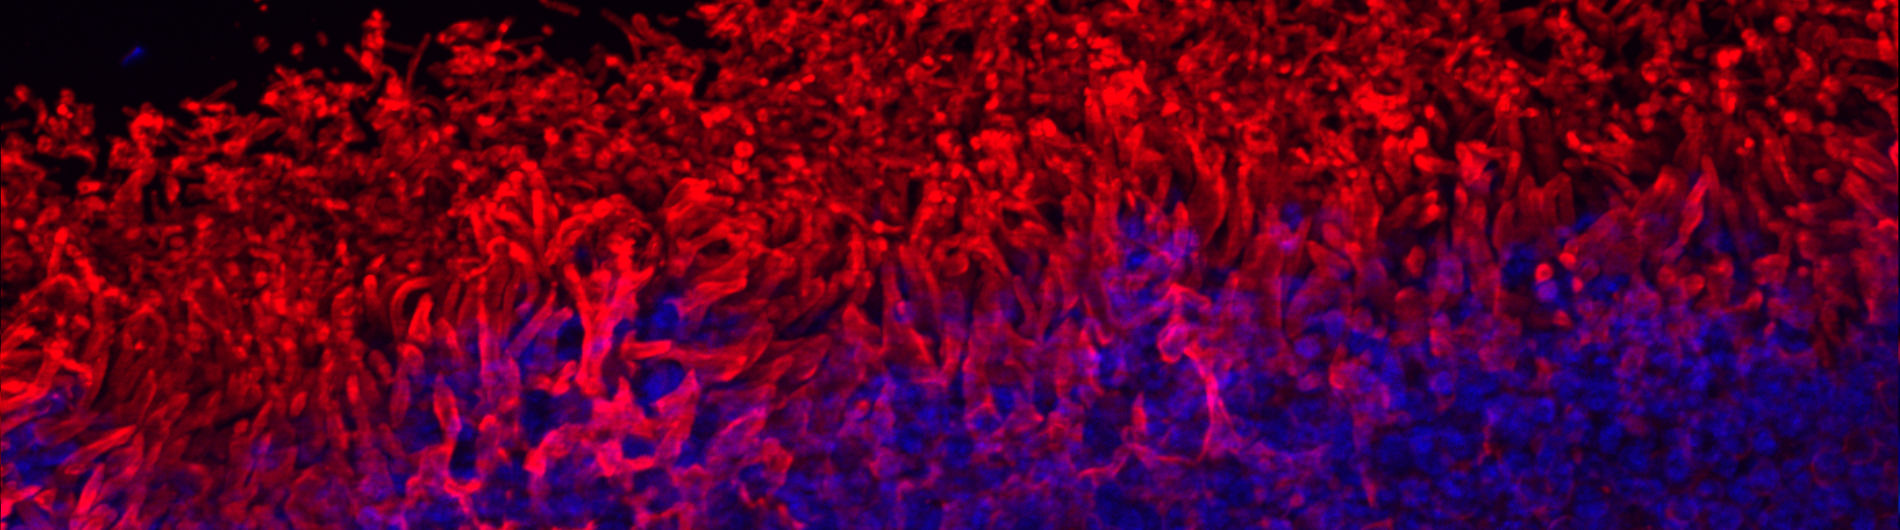

Dysfunction of any of the cell types that reside in the retina or supporting cells, the retinal pigmented epithelium (RPE), which is vital for the health of the retina, will disrupt vision - our aim is to determine the mechanisms that cause such disruption and find ways to repair the damage.

A schematic diagram of the retina (Mellough et al. Stem Cells. 2009 Nov;27(11):2833-45).